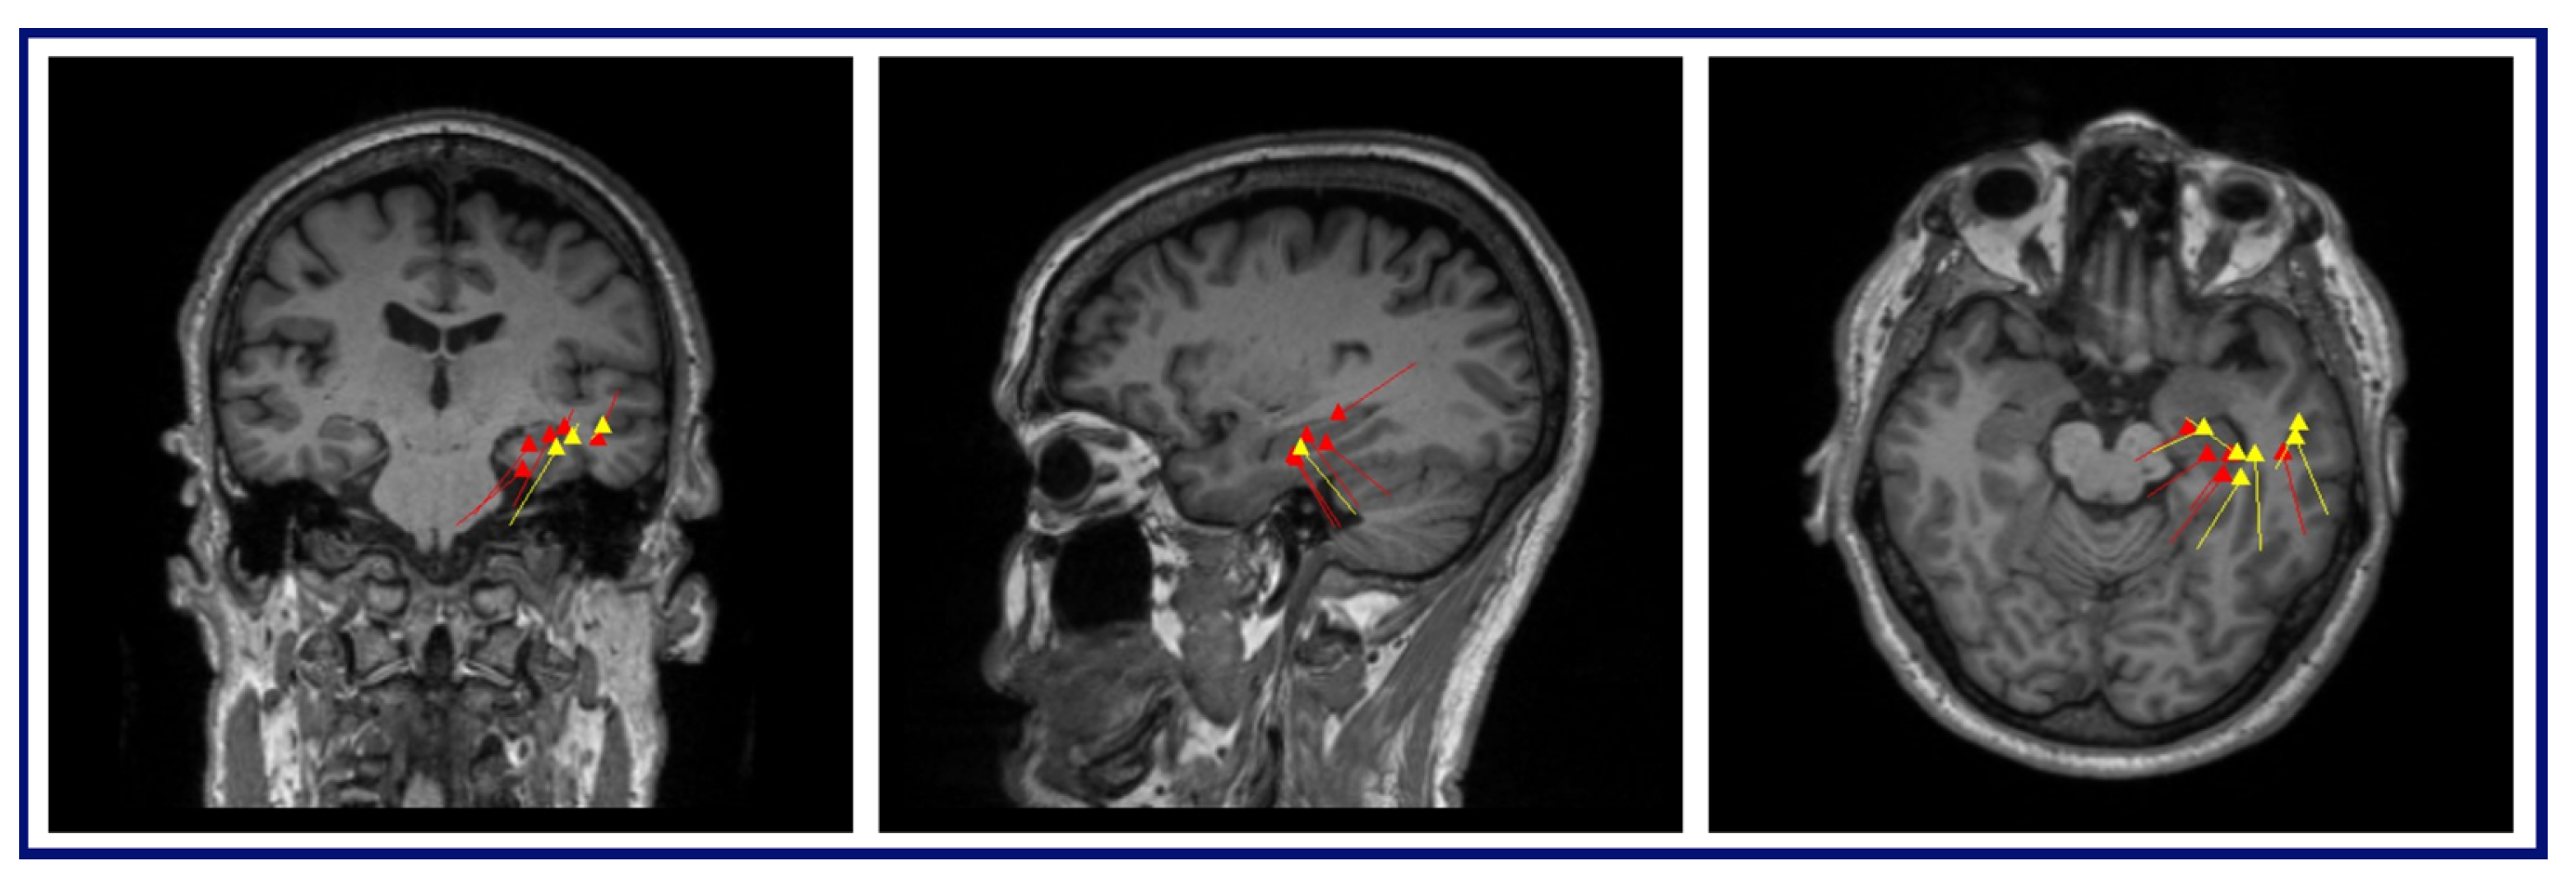

The MEG results for this patient were as follows: (A) Conventional preprocessing—tight clusters in the left precentral and postcentral gyri, the latter bordering the large artifact area, and a loose cluster in the left anterior insula, inferior frontal operculum, and middle frontal gyri. (B) ICA-based preprocessing—a tight cluster in the left inferior frontal gyrus and precentral gyrus, a loose cluster in the insula and Rolandic operculum, and isolated dipoles in the cingulate gyrus, the SMA, and the middle and superior frontal gyri within, or bordering on, the dysplastic area (Figure 5).

Figure 5.

MEG dipole analysis: A comparison of dipole analysis between conventional and ICA-based preprocessing techniques on Patient 1. This figure illustrates that the dipoles (represented by yellow lines and triangles) fitted with the ICA-based preprocessed data show diminished association with the RNS device artifact area and increased concordance with the hypothesized seizure onset zone (left inferior frontal and precentral gyri) compared to conventional preprocessing.

Dipoles fit with the ICA-based processed data demonstrated a reduced relationship with the RNS artifact area, i.e., the clusters and dipoles localizing to areas well-distinguished and further from the area of the RNS device, demonstrating less interference from the artifact. In the case of Patient 1, the conventional preprocessing showed tight clusters in the left precentral and postcentral gyri, bordering an area on the MRI showing a large artifact from the RNS device. However, with the ICA-based preprocessing, the tight cluster was found within the left inferior frontal and precentral gyri, with isolated dipoles localizing to the SMA, and bordering or within the dysplastic frontal lobe area, suggesting a more accurate localization within the clinically relevant regions of interest. Similarly, in the case of Patient 2, the conventional preprocessing showed dipoles bordering or within the large artifact area in the left frontal lobe. In contrast, the ICA-based preprocessing revealed two tight clusters in the left inferior frontal gyrus and left insula, with two additional dipoles within the left middle frontal gyrus. The results of the ICA-based processing were overlapping SOZs detected by the previous invasive study. In summary, the ICA-based preprocessing for the MEG results provided information that was more consistent with other imaging findings, clinical information, and epileptogenic zones identified by SEEG.